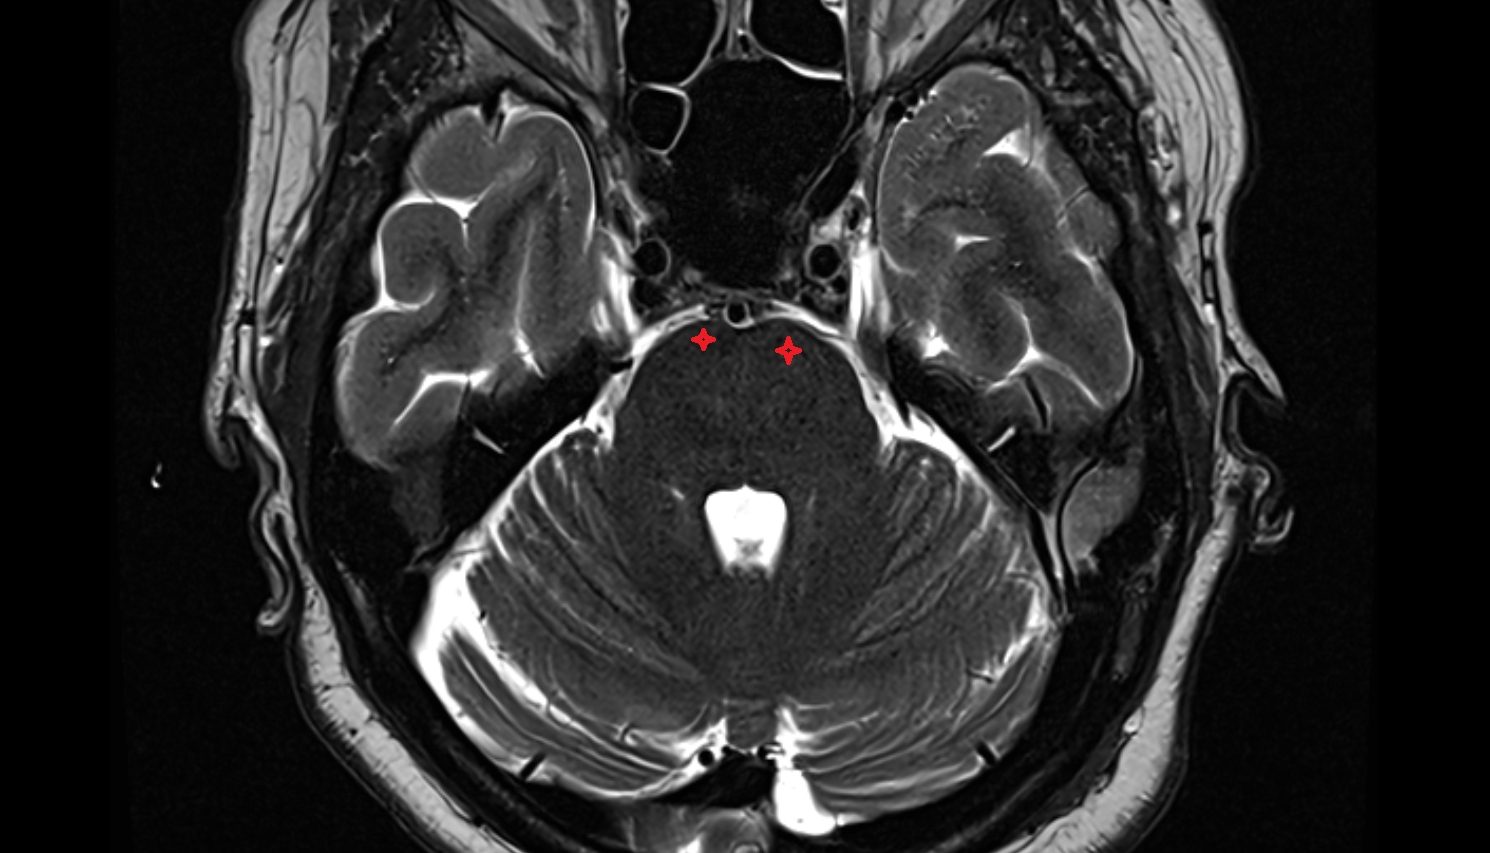

- Pontocerebellar cistern